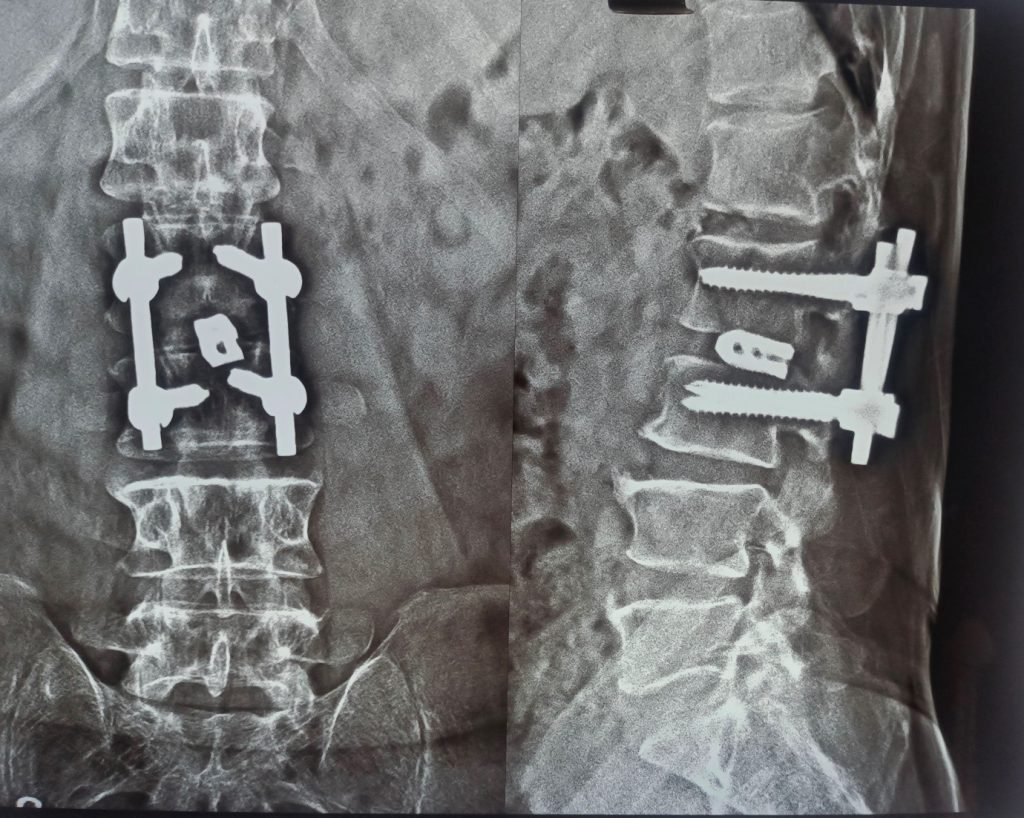

- Urgent spinal decompression surgery

- Placement of titanium disc/cage, when required

- Spinal stabilization with titanium rods and screws for long-term stability